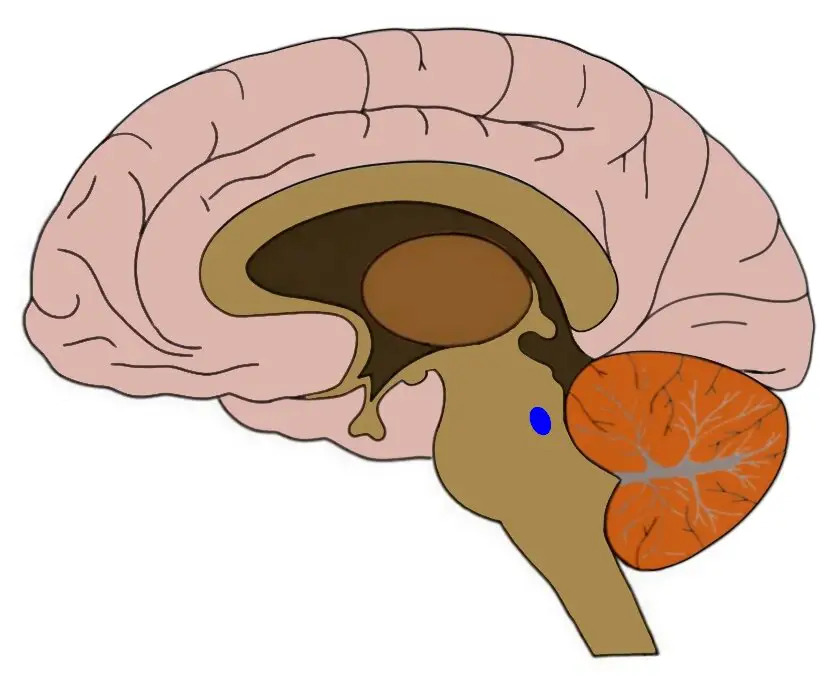

This small brain nucleus, the size of a 2cm-long spaghetti, is located at the base of the brain (in the brainstem).

The locus coeruleus — Latin for “blue spot” — owes its name to its colour when observed in autopsy. It projects to just about every area of the brain (and to the spinal cord) to secrete a neuromodulator called noradrenaline, which is not only important for stimulating neurons and keeping them awake, but also for a whole series of cognitive processes such as memory, emotional processing, stress and anxiety.